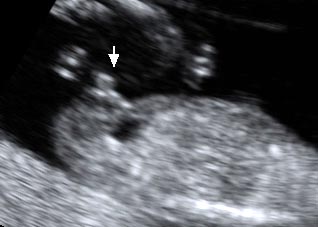

香港结构超声波照片

结构性超声波, 四维 香港, 四维结构性超声波 结构性超声波, 四维 结构性超声波, 四维 香港, 四维结构性超声波 结构性超声波, 四维 香港, 四维结构性超声波 结构性超声波, 四维 结构性超声波, 四维 结构性超声波, 四维 香港, 四维结构性超声波 结构性超声波, 四维 香港, 四维结构性超声波 结构性超声波, 四维 结构性超声波, 四维